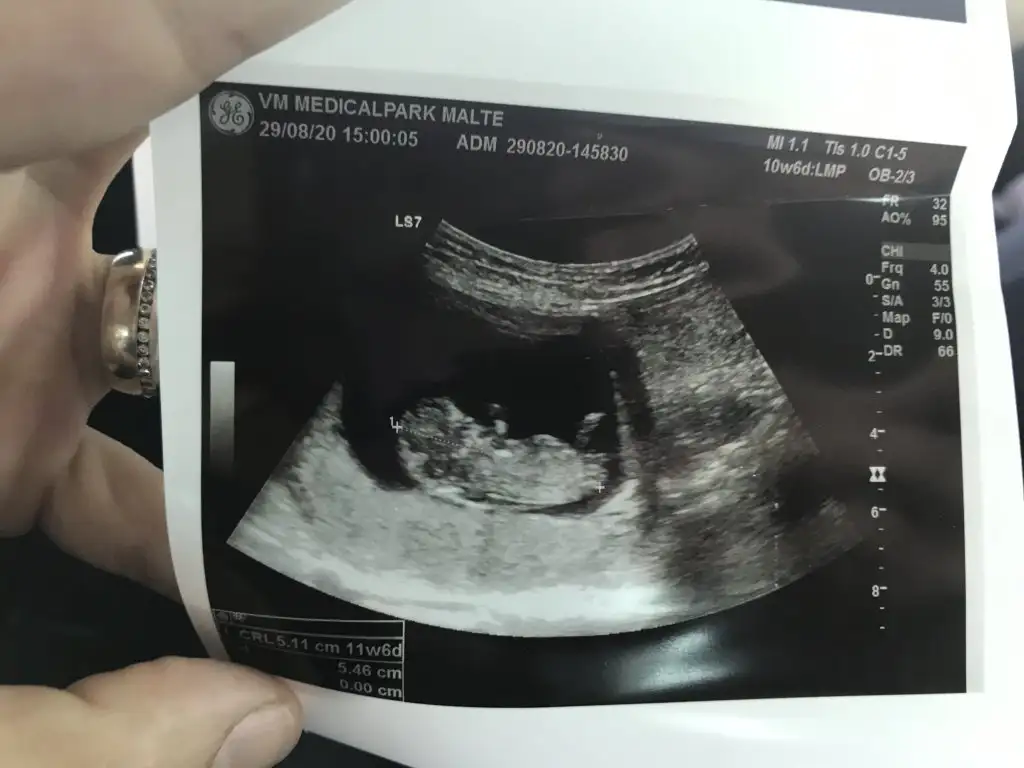

Kiza benzettim benIkra meyra canım bakabilir misin. 12+4

Keseye göre hep kız demişlerdi. İlk defaKiza benzettim ben

Doktorda kıza benziyor dedi canım :) tam net öğrendiğimde yazacam inşallahKız demistimWonria ogrendinizmi